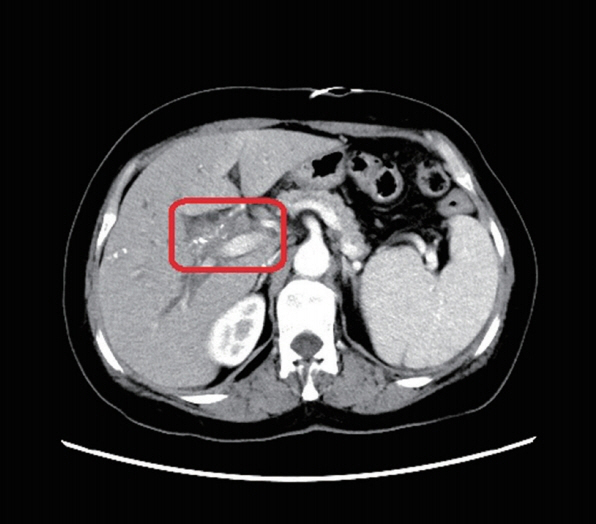

Fig. 2The abdominal and pelvic CT scan showed that thickening of the bile duct wall in the hilus (red box marker site).